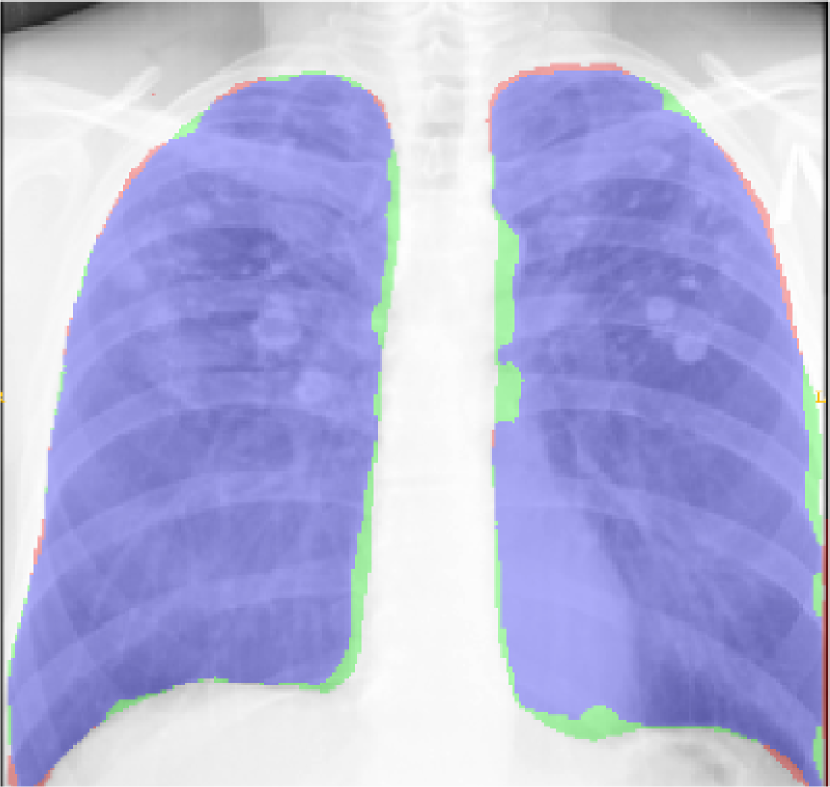

Fig. 9 presents the qualitative results of performing the lung segmentation using the proposed pipeline (ESL+MaShDL). The figure provides a visual insight on how inclusion of retro-cardiac region results in the segmentation label that is independent to the shape and structural changes in the close-by anatomical structures such as heart. For comparison purposes, similar qualitative results for the lung field labels obtained using the method proposed in [11] are provided in Fig. 10. As predicted before, the shape specificity is not preserved for the lung field labels obtained using [11]. This is further evident through the results presented in Table II. Moreover, unlike the proposed method, the U-net architecture uses an overlapping-based objective function (e.g., cross-entropy) which provides satisfactory results in cases with reduced shape variability. However, in the particular case of thoracic radiographs, the lung field labels without retro-cardiac space present higher shape variability than those observed when including this region. This could be a possible explanation of a slightly better overlapping-based performance (i.e., Overlap and DSC) by U-Net [11] when including the retro-cardiac space than without including it.